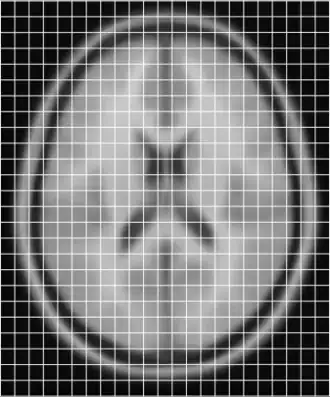

To get an idea of how they currently overlay I have put them together below

combined individual and model images

Clearly they are not aligned or "registered" to each other so we have to use a tool such as minctracc or mritoself in order to align them as such: